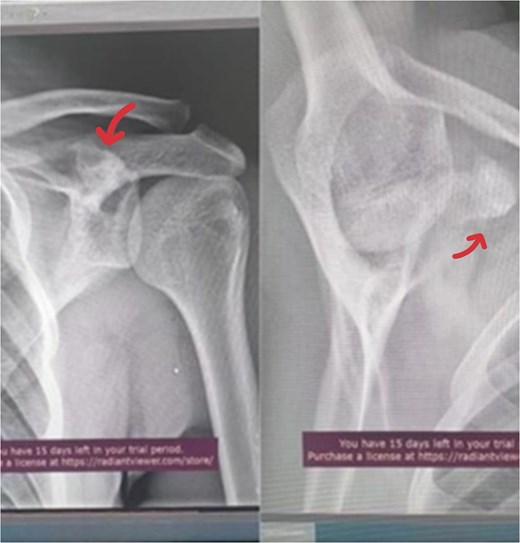

A 17-year-old male presented with left shoulder pain and limited range of motion for 2 months, with no history of trauma or prior medical or surgical issues. On examination, there was tenderness localized to the coracoid process. Initial laboratory tests, including complete blood count (CBC), C-reactive protein (CRP), and erythrocyte sedimentation rate (ESR), all normal. Conservative management with rest and non-steroidal anti-inflammatory drugs (NSAIDs) was initiated, but there's no improvement. Initially, imaging with an X-ray revealed a suspicious lesion at the base of the coracoid process (Fig. 1), prompting further evaluation with magnetic resonance imaging (MRI) without contrast, which confirmed the lesion in the base of the coracoid with surrounding fluid and edema extending to the coracoid-humeral space (Fig. 2).

AP radiograph of the left shoulder shows a suspension lesion in the coracoid process of the scapula (indicated by arrow).